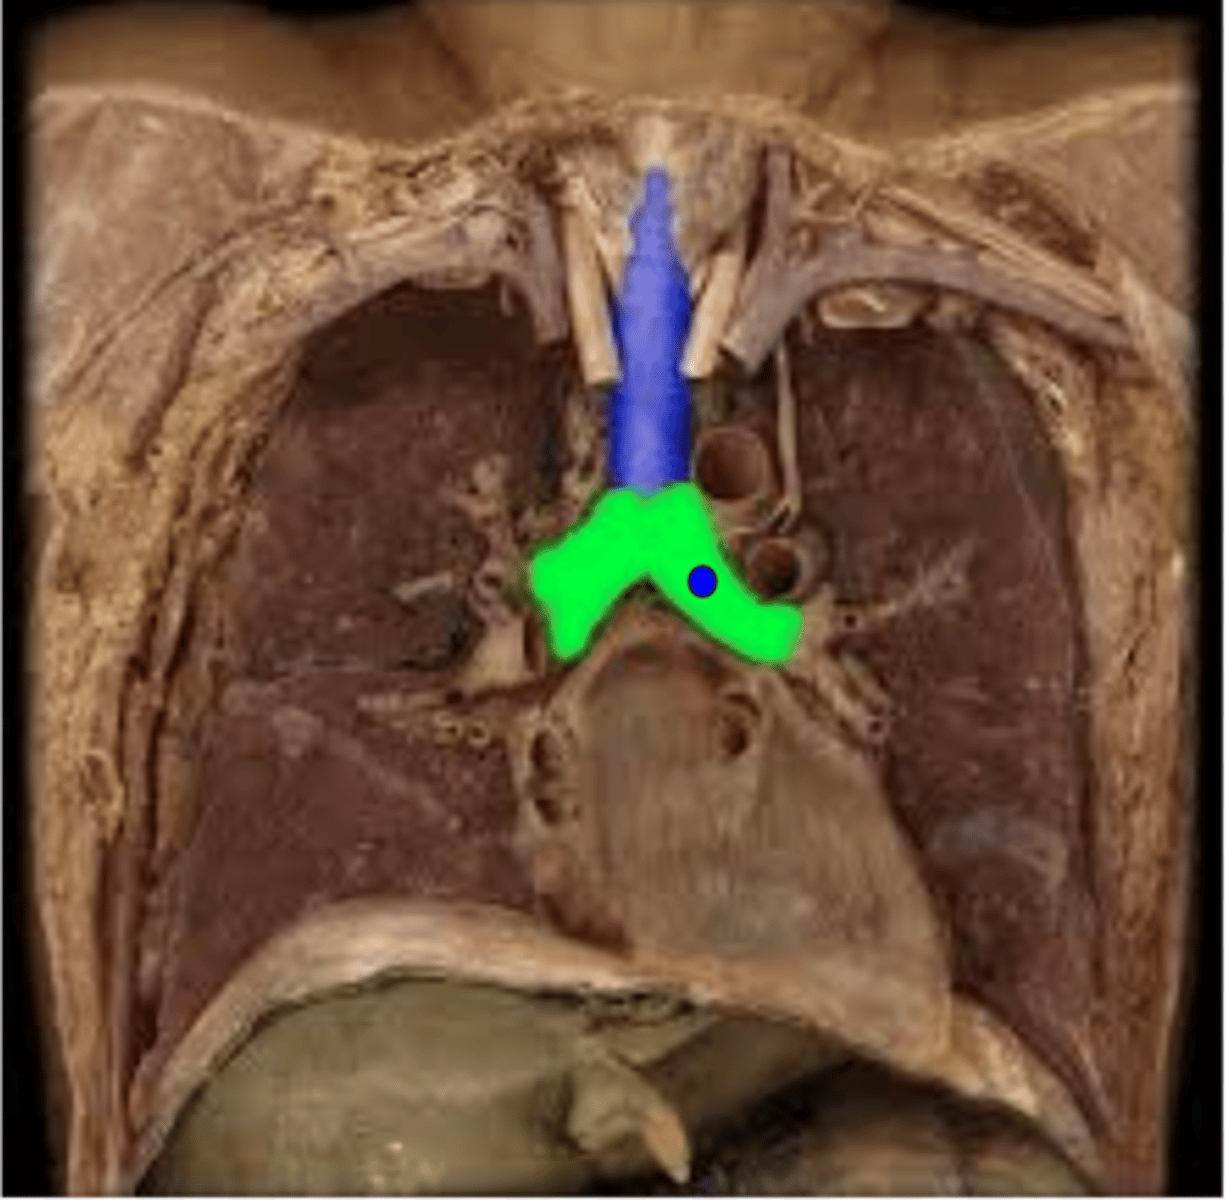

Trachea

Carina

Right Primary Bronchus

Left Primary Bronchus